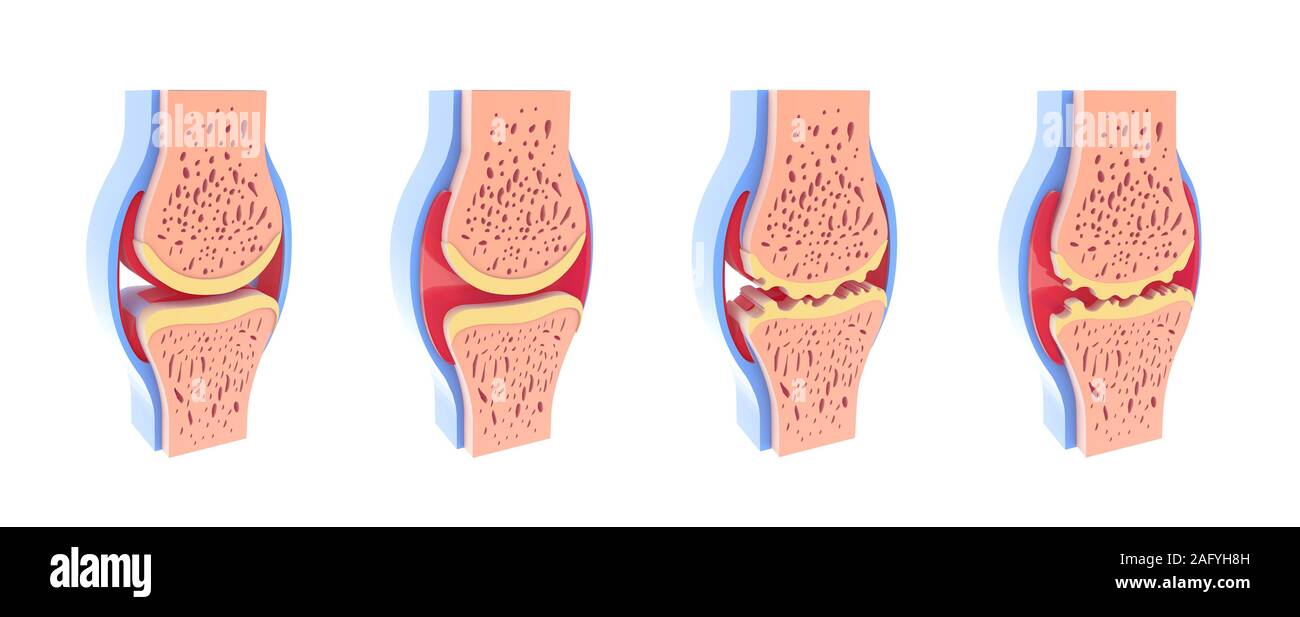

3d illustration of healthy and spherical synovial joint. In four representations standing and isolated on white background. Stock Photohttps://www.alamy.com/image-license-details/?v=1https://www.alamy.com/3d-illustration-of-healthy-and-spherical-synovial-joint-in-four-representations-standing-and-isolated-on-white-background-image336823105.html

3d illustration of healthy and spherical synovial joint. In four representations standing and isolated on white background. Stock Photohttps://www.alamy.com/image-license-details/?v=1https://www.alamy.com/3d-illustration-of-healthy-and-spherical-synovial-joint-in-four-representations-standing-and-isolated-on-white-background-image336823105.htmlRF2AFYH8H–3d illustration of healthy and spherical synovial joint. In four representations standing and isolated on white background.